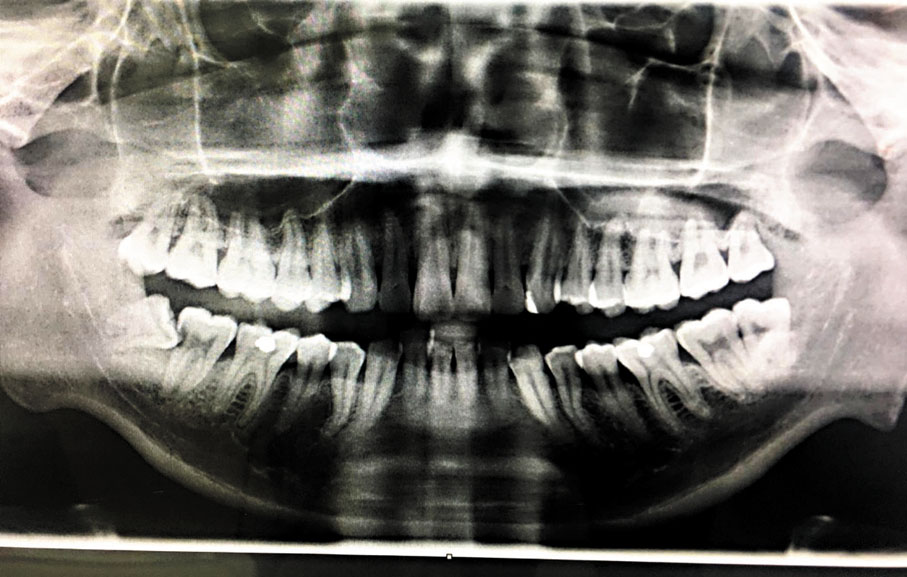

因此,為了進一步證明,我再具體舉一例,那我先從X光片說起。

有否留意黃色圈右邊的牙齒不向上伸展,而是橫向頂向其他牙齒。而上文已闡述了牙齒,堅硬細緻的特性在姓名中即頭身腳的頭部(姓氏)就是牙齒。這學生的姓氏是方姓,就是辛金,即尾門基因蛋白質修飾的格式。而不正常橫向的走勢,在數理上就是辛金被不知名的力量向右推的數理原因,就是乙與辛沖,沖即動也。所以,根據力留常理,乙木向辛金推動的方向,自是不難發現辛金牙齒的底部有乙向左推,而頂部則向右推。

至於風水原因,前文也提到大門兩側的牆壁,就是牙骨,而牆壁前的可動傢俬就是牙齒。見大門的右邊有一雜物房,而在側面的櫃門被電掣過路箱頂住,櫃門無法向大門方向開啟,以最短最自然的原則搬動房內傢具變得不可能了,即代表最自然的牙齒生長成了必須向不正常方向才可取出來了!

唯有向金色手柄那邊門搬出來了﹗

而另一邊的雜物則可隨意向大門方向取出。